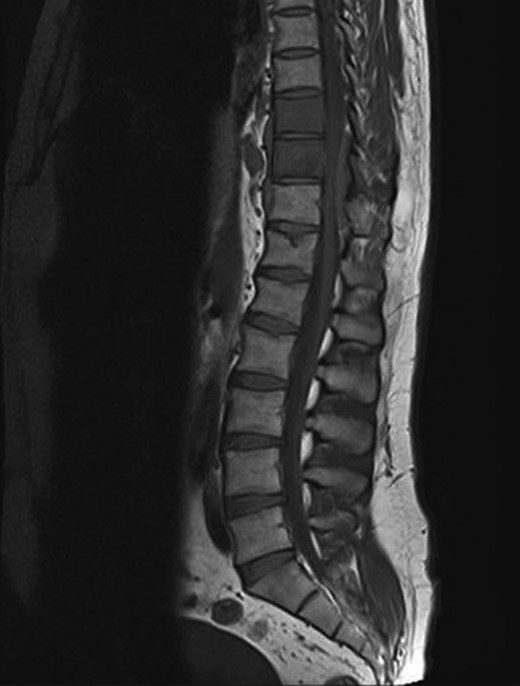

A 30-year-old male patient was admitted to our clinic with back pain. Pain was provoked by movements. The severity of pain was associated with the inability to perform the activities of daily living. The patient did not have any lymphoma-related B-type symptoms, including body weight loss, fever and sweat at night. He did not have a past and family history. There was no neurological deficit. Routine laboratory test results were normal. A magnetic resonance imaging (MRI) scan of the thoracic spine demonstrated an epidural tumor at the T9–11 level (Figs 1–3). The patient underwent spinal cord decompression via total laminectomy of T9–11 levels. Subtotal resection of the tumor was performed. Histological examination revealed the polymorphous cellular infiltration by histiocytes, large mononuclear cells and lacunar Reed–Sternberg cells with folded multi-lobed nuclei and small nucleoli (Fig. 4). Immunohistochemical staining was positive for CD15 and CD30 and negative for CD3, CD20, CD79a or CD45Ro. These features were most frequently observed in the mixed cellularity type of Hodgkin's lymphoma. Histological examination of the vertrebral body revealed no abnormality. The results of all other examinations (F-18 fluorodeoxyglucose positron emission tomography (F-18 FDG PET/CT), bone marrow biopsy and computed tomography (CT) of the chest, abdomen and pelvis) were negative for an occult disease. The patient was referred to the hematology department to undergo staged treatment. Six courses of chemotheraphy containing ABVD regimen (adriamycin, bleomycin, vinblastine and dacarbazine) were given to the patient. Postoperative MRI scan did not reveal any evidence of Hodgkin's disease (Fig. 5), F-18 FDG PET/CT, CT of the chest, abdomen and pelvis were obtained in 24 months and did not reveal any evidence of Hodgkin's disease.